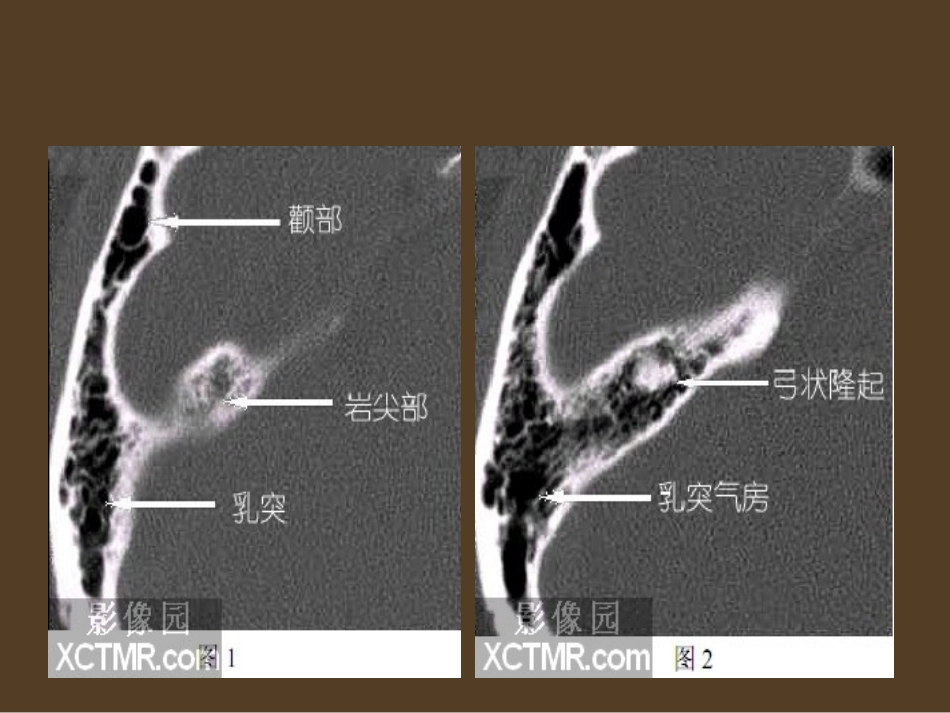

耳部解剖•耳部疾病的诊断除了临床体格检查、听力检查、前庭功能检查外,影像学检查越来越成为诊断治疗中必不可少的手段。随着CT、MRI的普及,耳和颞骨影像学检查已成为耳和侧颅底临床常规的辅助诊断项目。•CT对骨和钙化组织显影清晰,可兼顾骨与软组织的显示,在一般耳部疾病的应用中价值较高。MRI可多轴向成像以提供全面观察;可避免骨质干扰骨管腔内细小软组织结构的显示,而且对软组织特性反映较好,故常用于耳、内听道、侧颅底肿瘤的软组织病变检查。CT观察骨结构以骨算法扫描最为清晰,如用普通扫描则应加骨窗(扩大窗宽,提高窗平)显示,以利观察细小骨质改变。•耳部CT常用轴位和冠位,本期重点介绍耳部轴位CT检查。耳部轴位又称水平位,病人仰卧,取听-毗线,于外耳孔上方10mm处,可用130KV、100MA、3-6S、1-3MM层厚和间距用骨质窗位条件,往下连续扫描,要求扫完整个岩锥。横断面CT对于外耳道前后壁、中耳前后内外壁、听小骨、内耳道前后壁、内耳迷路、面神经膝部和垂直段、乙状窦、静脉孔及颈动脉管等结构显示较清楚。由于头位的关系,显示的结构有时二侧不对称,需要以同一平面进行对比。这里仅就典型的层面进行讨论。•图1.-图4.显示岩尖部和上半规管。•图5.起出现内听道。图6.出现耳蜗顶旋,同时在内听道外侧有一通向上鼓室的通道,是面神经迷路段。内听道的听神经到达耳蜗为止,前庭神经止于前庭和半规管,唯有面神经向鼓室方向延伸,形成面神经迷路段。•图7.的重要结构为面神经出迷路段后有一膨大区,为膝状神经节,由此向前有一分支为岩大浅神经,向后为面神经鼓室段,此结构呈“T”型,垂直于岩大浅神经和面神经鼓室段的是面神经迷路段。前庭和后半规管在此层面出现,同时出现颈内动脉的升段。•图8.为典型的前庭层面。在上鼓室出现锤砧关节,呈冰淇淋(Ice-cream)样结构,前端似冰淇淋的是锤骨头,后方似蛋桶状的为砧骨体。耳蜗内侧可见面神经鼓室段。在后半规管的内侧有一与之平行的裂隙,为前庭导水管,一般不超过1.5mm宽。在较大的前庭腔后外侧,有与之相通的半弧形的水平半规管腔。•图9.耳蜗中旋出现。颈内动脉管水平部初现,面神经鼓室段向后延伸至水平半规管。•图10.在面神经鼓室段的外侧可见有小的隆起为匙突。同一平面出现开放的面神经外膝部,又称锥曲部,由于骨壁薄,呈向鼓室的开放状,文献报道此处面神经的自然裸露率达17~37%。后鼓室显示内侧的鼓室窦(sinustympani)和外侧的面隐窝(facialrecess)。鼓室内锤骨柄和砧骨长突可见。•图11.平面为典型的耳蜗层面,耳蜗的上中下旋在一个平面共现,耳蜗底旋初现,圆窗龛和其内侧的圆窗间隙清晰。砧镫关节在此层面出现,可见镫骨板上结构和部分底板。面神经锥曲段呈椭圆形,是面神经由鼓室段向乳突段上升时被断层斜切所致。•图12.此层面出现外耳道,锥隆起显示明显。耳蜗导水管为一细缝隙与外耳道方向平行,由外向内(前庭导水管由内上向后外方向).耳蜗仅见宽大的底旋。•图13.-图14.颈动脉管水平段全程出现,耳蜗中旋和底旋明显,在耳蜗后方有一个膨大的圆形前庭腔,在前庭腔内侧可见后半规管的膨大壶腹。耳蜗外上方有一细长的鼓膜张肌管腔,其后方的小突起是匙突。外膝部的面神经由于骨壁薄呈开放状。有报道此处面神经有17~47%的自然裸露率,手术时应当注意。上鼓室外上有一小的骨嵴称齿突(cog),其前方是前上鼓室,后方容纳锤骨头和砧骨长突,前上鼓室是胆脂瘤经常侵及的部位。图14外耳道出现。•图15.鼓膜张肌管明显。耳蜗仅见底旋,在耳蜗底旋后方可见圆窗和圆窗龛。面神经渐渐向乳突内移,其面向中耳腔的开放处是镫骨肌处。镫骨肌的内外分别是鼓室窦和面隐窝。耳蜗内侧水平向内的一个细狭管腔是耳蜗导水管。•图16.耳蜗底旋内侧水平走向的耳蜗导水管清晰,面神经管在乳突内呈密闭的圆形管腔,与鼓室不通,面神经全部到达乳突段。该层面颈动脉管外前方的细长管腔是咽鼓管,其形态与上一层面的鼓膜张肌管相似。鼓室窦和面隐窝分别在锥隆起的内外二侧。此层面外耳道开始宽大。•图17.面神经乳突段呈圆形管腔,耳蜗仅底部无管腔,耳蜗导水管开口宽大,临近耳蜗导水管内侧是颈静脉孔。颈动...